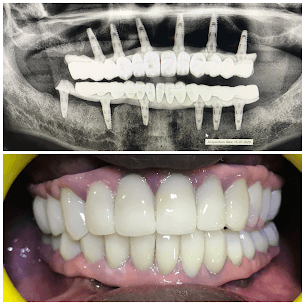

Malo Bridge Implants

Implant treatment for 40-year-old with atrophied ridge using titanium frame and zirconia crowns